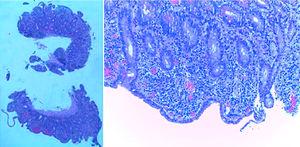

The histologic examination (fig. 2) showed subtotal villous atrophy with lymphocytic infiltration in the lamina propria. The prothrombotic factor study was negative.

Normocytic normochromic anemia and hypoalbuminemia are the most frequent laboratory abnormalities at presentation. Upper endoscopy may be normal, or show a nodular appearance of the duodenal mucosa. The most common histopathologic finding is flattening of the duodenal villous pattern (either total or partial) and increased duodenal intraepithelial lymphocytes (IELs). Contrary to celiac disease, flattening of the duodenal villous pattern is not always associated with IELs1,3–7.